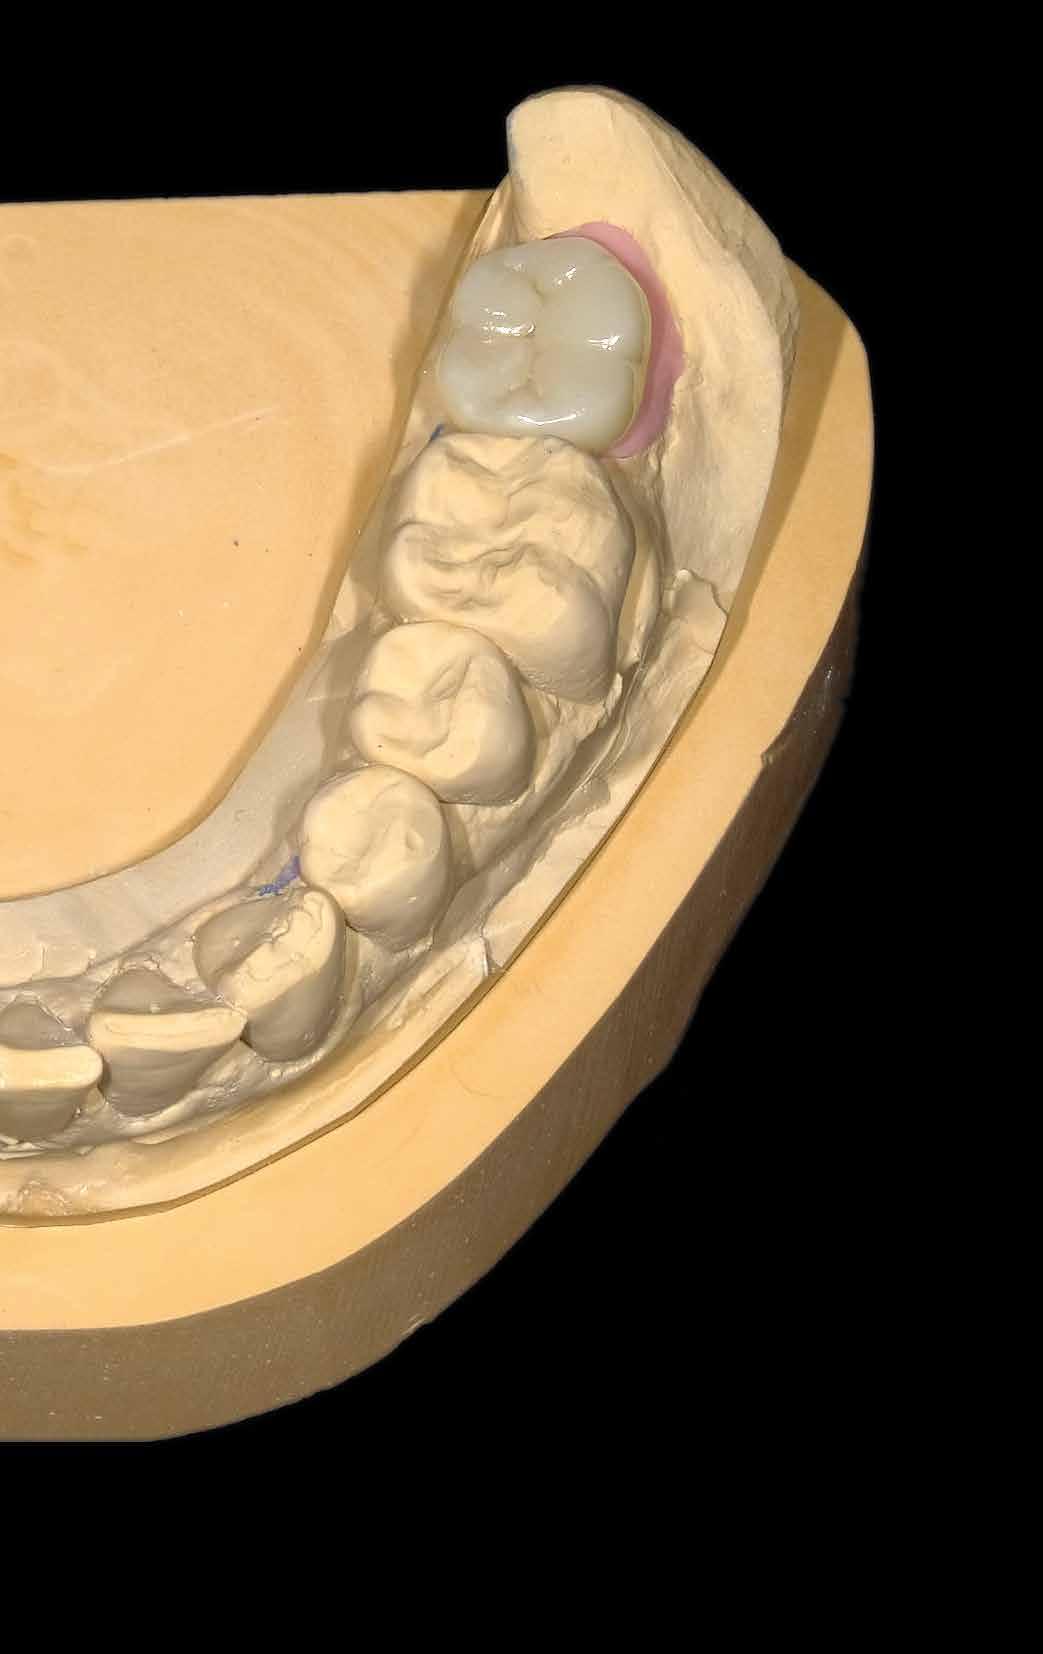

30–33. ábrák: A kész, adhezívan összeragasztott, polírozott multilayer restauráció.